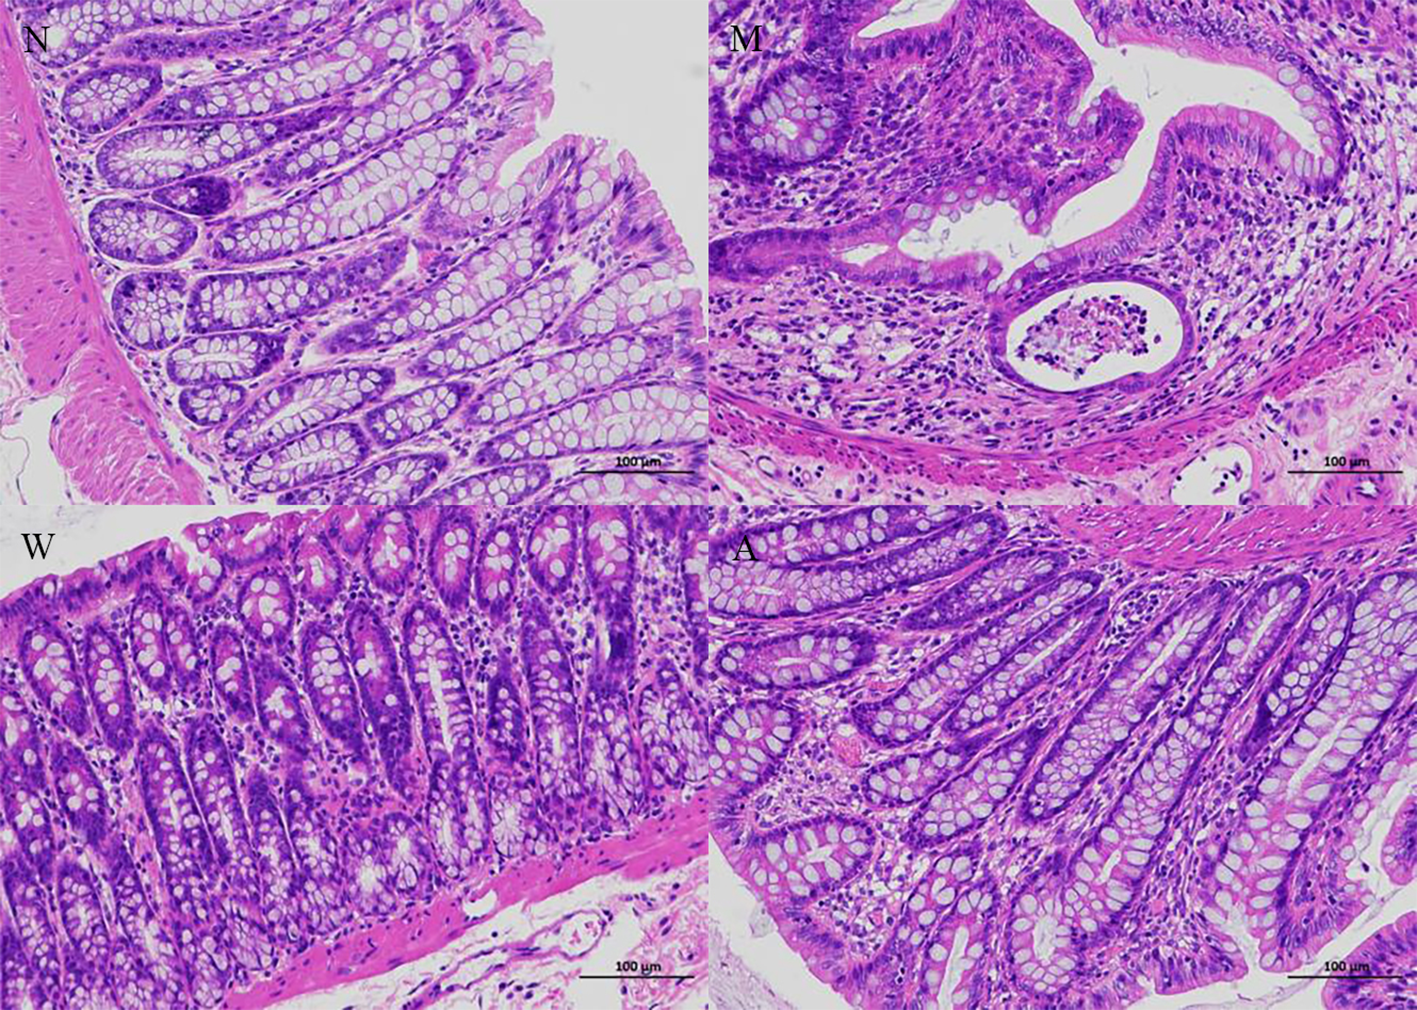

As shown in Figure 2, the colonic tissue was stained with HE staining and observed under a microscope. The colonic mucosa of the rats in the normal group was intact, the cells were neatly arranged, the glandular structure of the lamina propria was normal, and there was no infiltration of inflammatory cells. Instead of normal cells, goblet cells decreased, the crypt structure was disordered, crypt abscesses appeared, and glands atrophied; the structure of the colonic mucosa of rats in the mesalazine group was basically restored, the cells were arranged regularly, the gland structure was relatively complete, some parts were still visible, and some inflammatory cells infiltration can still be seen; the colonic mucosa of the rats in the artemisinin group was relatively intact, the cells were arranged regularly, the intestinal gland structure returned to normal, and a small amount of inflammatory cells infiltration ware seen.

Figure 2

Histopathology (magnifification 200×). N, normal group; M, rats treated with 3.5% DSS alone; W, rats treated with DSS plus mesalazine (315 mg/kg); A, rats treated with DSS plus Artemisinin (100 mg/kg).

The experimental results indicated that the pathological changes in the colon of the DSS-induced UC rat model showed inflammatory cell infiltration, goblet cell edema and crypt abscess at the ulcer site. In this study, it was found that artemisinin effectively reduced the infiltration of inflammatory cells, congestion, edema and ulcers. The results indicate that artemisinin can alleviate colon damage of UC. In addition, DAI and CMDI scores are commonly used to evaluate UC (27). According to our experimental results, artemisinin significantly reduced the high DAI and CMDI values induced by DSS, which again shows that artemisinin can effectively alleviate the disease activity in rats. The above results support our further study on the mechanism of artemisinin in the treatment of UC.